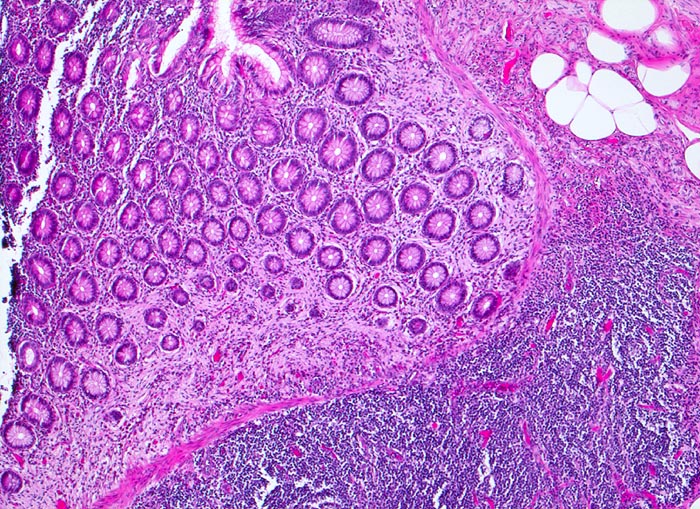

neurogene Appendikopathie Mukosaform

Appendix vermiformis

In den basalen Abschnitten ersetzt auffallend helles lockeres Gewebe die Kolonkrypten (proliferierte Nervenfasern).

Die neurogene Appendikopathie existiert in einer intramucosalen Form, als zentrales Neurom in einer narbig obliterierten Appendixspitze oder als neuromuskuläre Proliferation in der Submucosa.

Histologie

50